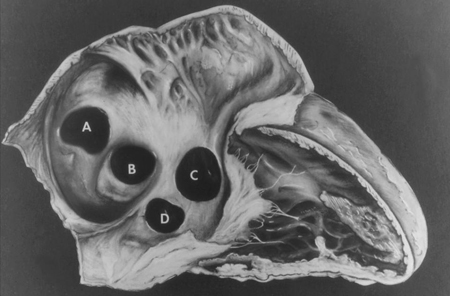

O DSV é a forma mais comum de CC, responsável por 20% de todos os casos, com exceção do prolapso da valva aórtica bicúspide e da valva mitral.[20] Os subtipos baseados na localização incluem: perimembranoso (na região da membrana septal); saída (abaixo de 1 ou ambas as valvas semilunares); entrada (inferior às valvas atrioventriculares [AV]); e muscular (na porção muscular ou trabeculada do septo ventricular).[21][Figure caption and citation for the preceding image starts]: Subtipos dos defeitos do septo ventricular: (A) saída; (B) perimembranoso; (c) entrada; (D) muscularMayo Clinic Foundation [Citation ends].